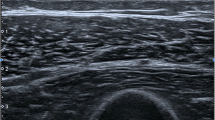

Shear wave elastography

The SWE system employed was the Aixplorer (Supersonic Imagine, Aix-en-Provence, France) system using the SuperLinear™ SL10-2 MHz probe, which has demonstrated substantial reliability in muscle SWE [12]. The muscles investigated were the four quadriceps (vastus lateralis [VL], rectus femoris [RF], vastus medialis [VM] and vastus intermedius VI]), the three hamstrings (biceps femoris [BF], semitendinosus [ST] and semimembranosus [SM]) and the biceps brachii (BB) of the most symptomatic side in patients and the dominant side in controls. These muscles were chosen as proximal lower and upper limb muscles, which are known to be commonly affected in IIM [20]. Positioning was as follows: resting supine on a flat bed with knees on full extension (rested quadriceps); elbow flexed at 90° with the forearm rested on the body and hand in supination (biceps brachii); prone on a flat bed with the knees flexed at 90° and rested on a wall (hamstrings). The quadriceps were also tested under passive stretching with the participants seated while the hips and knees were flexed at 90° without touching the floor. This was tested to evaluate if IIM muscle stiffness behaves differently under the passive load acted upon by the limb weight. Participants were instructed to relax their muscles in all positions and were rested supine for 5 min before scanning.

Two-dimensional SWE acquisitions were repeated three times per muscle and recorded as shear wave velocity (SWV) in units of metres per second (m/s). The probe was oriented along the muscle fibres and placed on top of the skin with a minimal load while ensuring no external pressure could deform the tissues and affect the measurements. The operator was blinded to the MRI and muscle assessment results.

Muscle shear wave elastography

The descriptive data for the SWV measurements are reported in Table 3. It shows the results of the independent sample t-test, which demonstrated a significantly lower muscle stiffness in IIM across all the quadriceps and hamstrings in the resting position (p < 0.05). In contrast, there was no significant difference for the BB or the quadriceps during passive stretching. The clustered boxplots in Fig. 1 graphically represent the SWV results for the various muscles of the two groups. Examples of SWE images from IIM patients and comparable controls are shown in Fig. 2. Sample size was too small to meaningfully compare SWV between IIM subtypes. Nevertheless, the inclusion body myositis patients showed no significant SWV difference from the other IIM patients (p = 0.24).